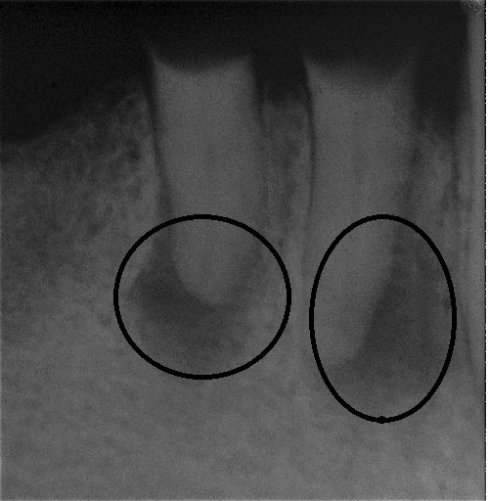

Wurzel nach erfolgreicher Behandlung 2 Monate später schon fast ausgeheilt